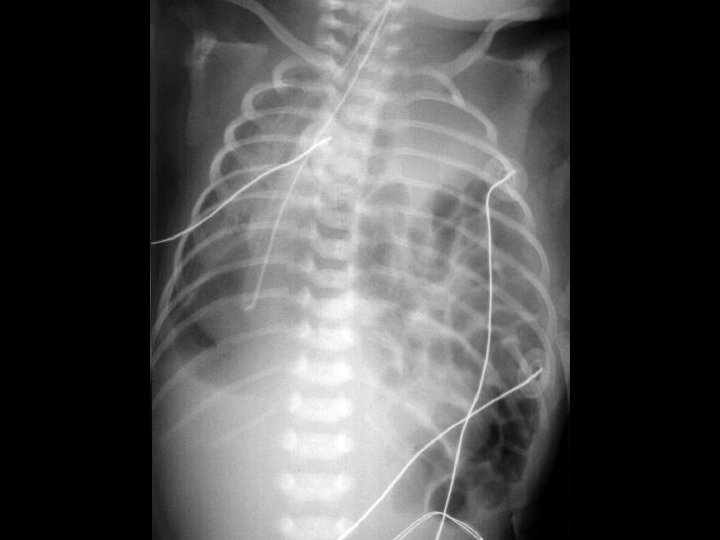

Case 1 Day 12 • On day 12 an Xray was done……

Case 1 Oh, oh…. . • On day 12…. – Free air noted on abdominal XR – No clinical abdominal symptoms • Rx…. – Intubated for transport – NPO – Antibiotic coverage expanded – Transported to Oakland Anna Bergquist CHO MR 960776